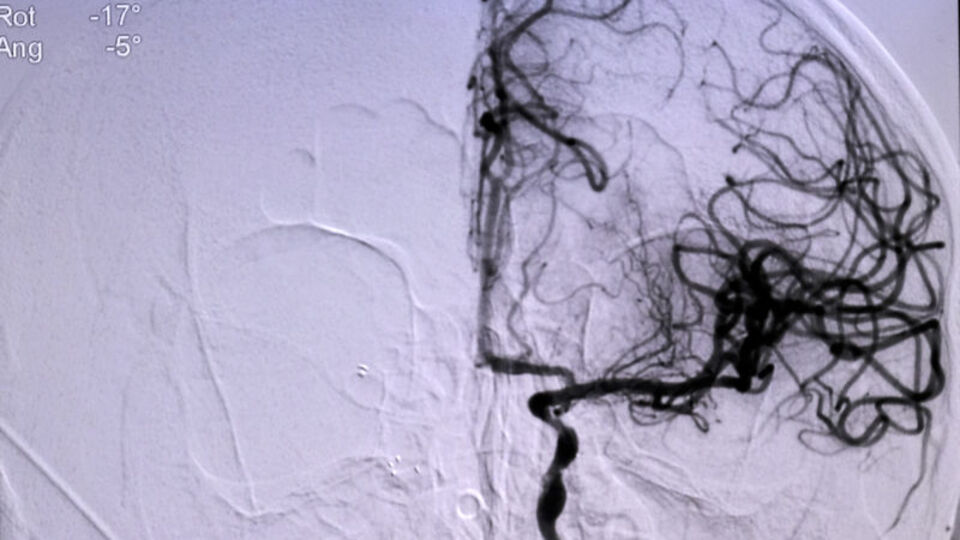

Niğde´den ellerinde uyuşma şikayeti sonrası başvurduğu hastaneden Konya'ya sevk edilen Ömer Altan´ın (73), kısa sürede müdahalesi yapılarak, tıkanan ana damarını açtıklarını belirten Doç. Dr. Gökhan Özdemir, "Hastamız Niğde şehrinden bize başvurdu. Oradaki hekim arkadaş hastayı değerlendirdi. Beyni besleyen ana büyük damarında ciddi bir darlığı tespit etti. Bu da hastanın felç geçirmesine sebep olan bir durum. Oradaki doktor arkadaş hızlıca bize ulaştı ve biz de hastayı kabul ettik. Bekletmeden burada hastanın müdahalesini yaptık, ana damarını açtık. Ana damar olduğundan dolayı bu hastaların büyük bir kısmı ölüyor. Yani beyni besleyen ana büyük damarlardan biri tıkandığı zaman genelde bu hastanın yüzde 50-60´ı ölüyor. Ölmese bile büyük ihtimalle ömür boyu özürlü kalacaktı" dedi.